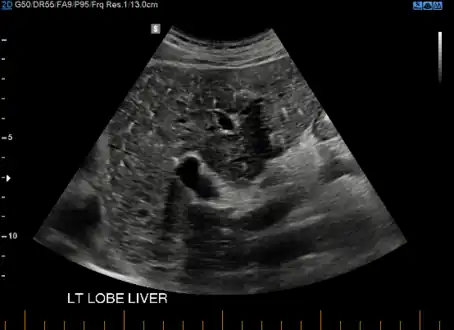

von Meyenburg Complex in ultrasound. Numerous little cysts with ringdown artefacts.

At CT scans, bile duct hamartomas appear as small, well-defined hypo- or isoattenuating masses with little or no enhancement after contrast administration.[2] At MRI, they appear hypointense on T1-weighted images, iso- or slightly hyperintense on T2-weighted images, and hypointense after administration of gadolinium based contrast-agent.[2] On imaging, multiple hamartomas may look similar to metastases or microabscesses.